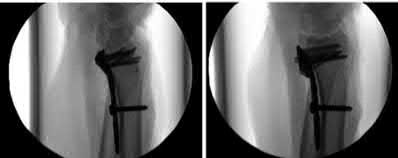

Question 19:

A 28-year-old male sustains a closed comminuted tibial shaft fracture. Two hours post-injury, he develops severe leg pain unyielding to narcotics. His blood pressure is 120/80 mmHg. Intracompartmental pressure monitoring is performed. Based on current guidelines, which measurement dictates an emergent 4-compartment fasciotomy?

Correct Answer: Delta pressure (Diastolic BP - Compartment Pressure) < 30 mmHg

Explanation:

Acute compartment syndrome is classically defined by tissue hypoperfusion. The absolute compartment pressure is less reliable than the differential pressure (Delta P). A Delta P (Diastolic Blood Pressure minus Compartment Pressure) of less than 30 mmHg is an absolute indication for emergency fasciotomy, as capillary perfusion gradient is lost when tissue pressure approaches the diastolic pressure.